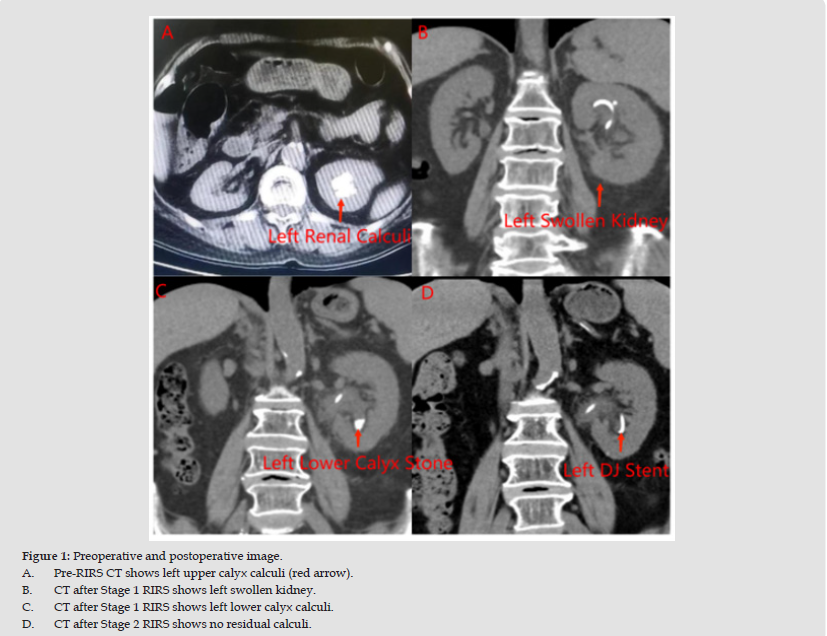

A 76-year-old female with a history of diabetes mellitus, hypertension, hyperlipidemia, chronic urinary retention, and post-stroke sequelae presented in July 2024 with left multiple renal calculi and recurrent urinary tract infections (Figure 1).

In September 2024, the patient experienced another episode of high fever and flank pain. Urine culture revealed extended-spectrum beta-lactamase (ESBL)-producing Escherichia coli, sensitive to cefoperazone- sulbactam. Anti-infective therapy was initiated, leading to symptom resolution. In October 2024, she presented with persistent low-grade fever. CT imaging revealed left renal swelling, a residual calculus (15 mm × 12 mm × 10 mm) in the lower calyx, and an indwelling DJ stent (Figure 1). Post-void residual urine volume was 115 mL. Inflammatory markers were elevated (CRP: 65 mg/L, IL-6: 90 pg/ mL). Based on her history and findings, recurrent pyelonephritis was attributed to VUR through the DJ stent. A urinary catheter was inserted to reduce intravesical pressure, and aspirin was discontinued.